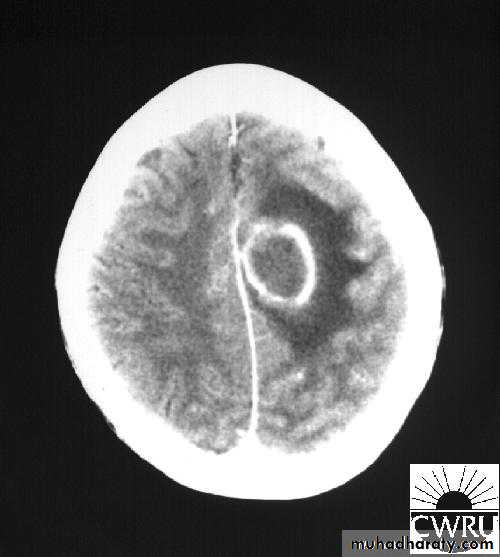

Stereotactic Aspiration of Brain Abscess